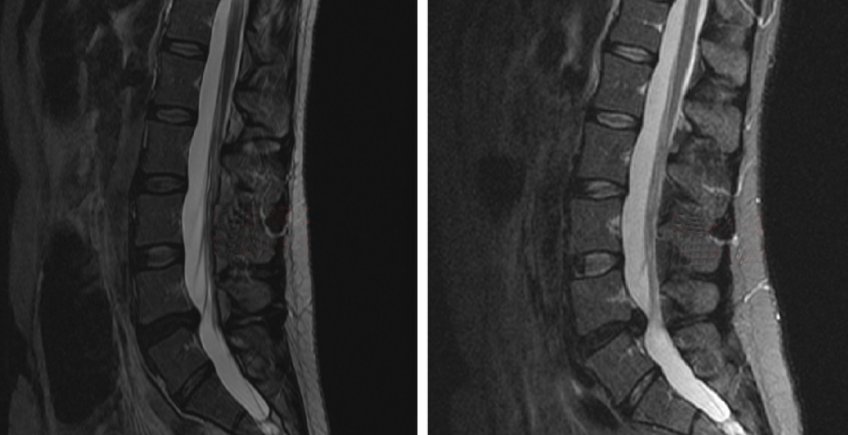

Hernia del Núcleo Pulposo (Protrusión)

Corresponde a la protrusión del material gelatinoso central de un disco intervertebral a través de una fisura en el anillo fibroso que lo rodea, este proceso se puede asociar a dolor lumbar por sensibilización de las terminaciones dolorosas y a dolor radicular derivado de la inflamación o compresión de la raíz nerviosa asociado o no a paresia o parestesia.